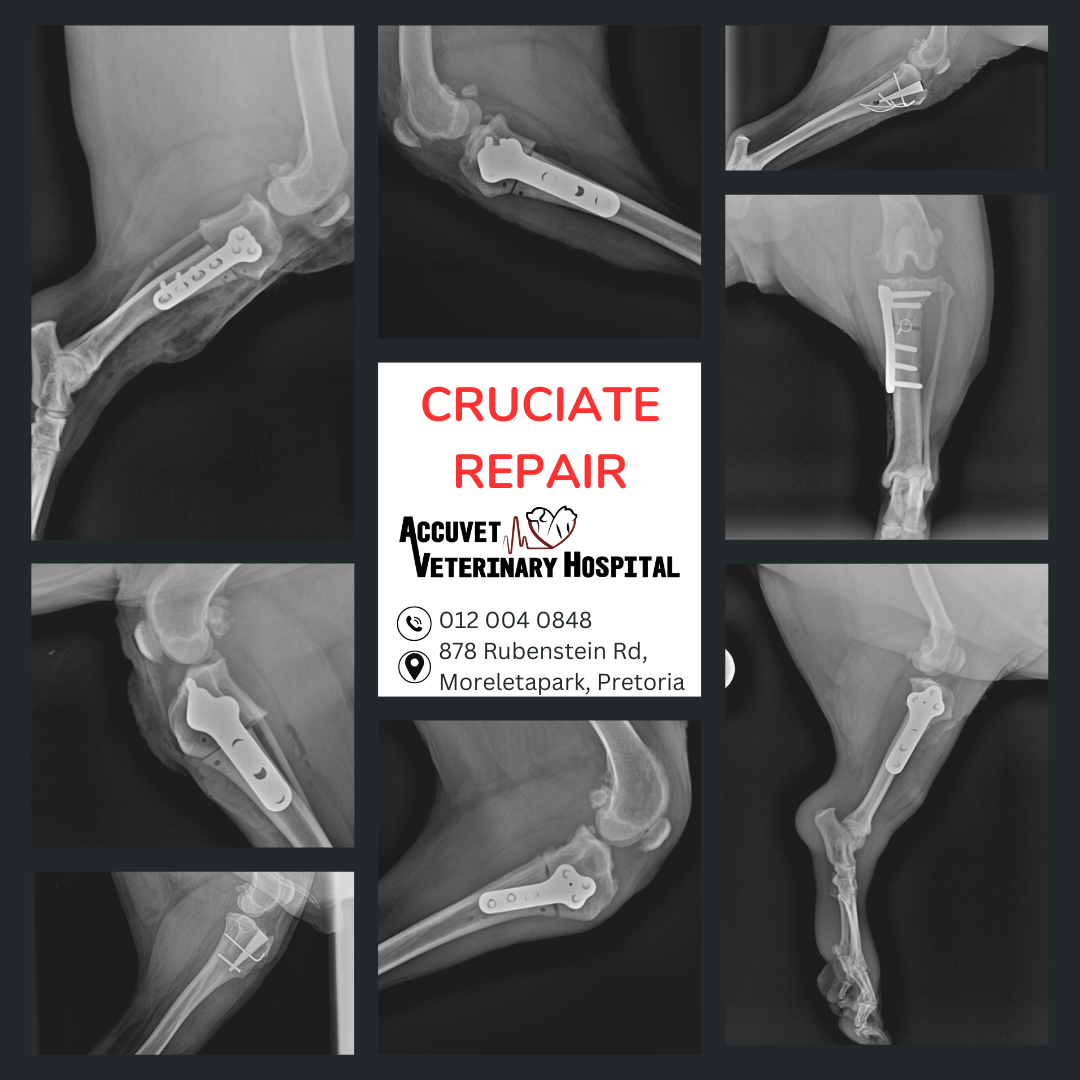

Cruciate Surgery (TPLO/CCWO/Extracapsular) One of the most common causes of hindlimb lameness in dogs is a torn cranial cruciate ligament (similar to an ACL injury in humans).

We’ll help you choose the right procedure based on your dog’s size, lifestyle, and specific needs. |